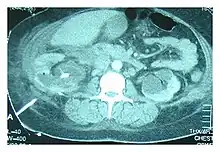

| Right sided pleural effusion caused by urinothorax | |